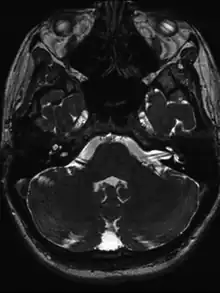

- MRI